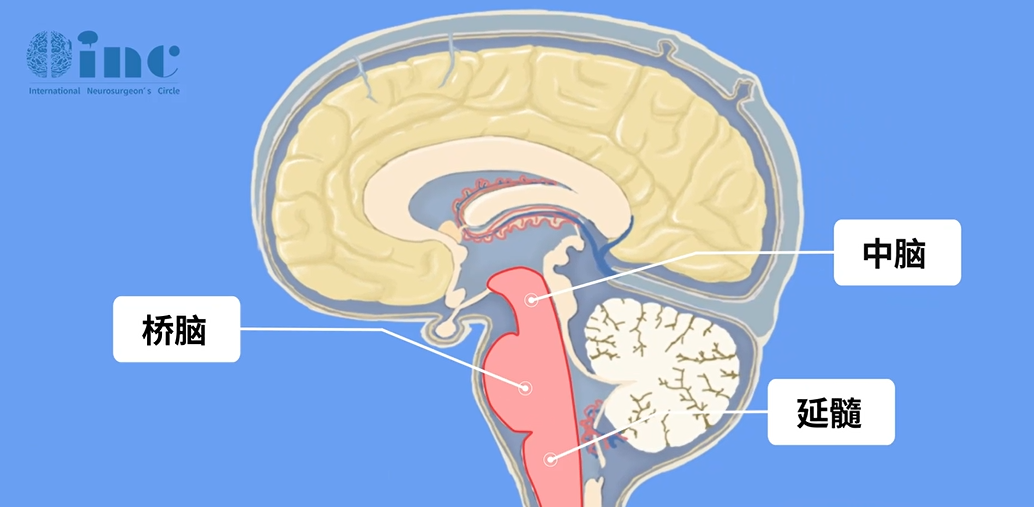

貝貝所患的腦干腦橋出血是神經(jīng)內(nèi)外科的危重急癥,腦橋出血量少時(shí),表現(xiàn)為突然頭痛、嘔吐、眩暈、復(fù)視、四肢癱瘓;出血量大時(shí),患者很快出現(xiàn)意識(shí)障礙、針尖樣瞳孔、四肢癱瘓、呼吸障礙、高熱,常可在48小時(shí)內(nèi)死亡。

腦干

而且腦干腦橋海綿狀血管瘤有反復(fù)發(fā)作性癥狀性出血的風(fēng)險(xiǎn),多次發(fā)作后會(huì)產(chǎn)生毀滅性的后果,對(duì)于患者的潛在威脅巨大??紤]到巨大的手術(shù)風(fēng)險(xiǎn),很多時(shí)候往往只能保守姑息治療,如果能及時(shí)手術(shù)切除病變?nèi)コ∫?,那患者往往可以獲得治愈性效果。手術(shù)的主要目的是切除病灶去除出血病因,消除反復(fù)出血風(fēng)險(xiǎn),此外,手術(shù)還旨在保護(hù)顱神經(jīng)、錐體束功能,避免引起面癱、肢體癱瘓等。